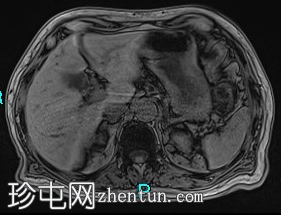

MRI

轴位T2加权像

脂肪抑制像

8.png

胰腺钩突附近可见边界不清的肿块,T2加权像呈不均匀中等信号,弥散受限明显。肿块大小为4.1 x 5 x 3 cm(前后径 x 横径 x 头尾径)。伴有胰管扩张,直径约6 mm。

肝脏可见多个大小不一的可疑病灶(从亚厘米级到2厘米不等)。T2加权像呈高信号,弥散受限明显。

远端胆总管突然变窄,但未完全阻塞。

胰腺周围可见多发囊性病变,部分与主胰管相连,提示胰腺导管内乳头状黏液性肿瘤(IPMN)。

双侧胸腔积液,左侧较多。